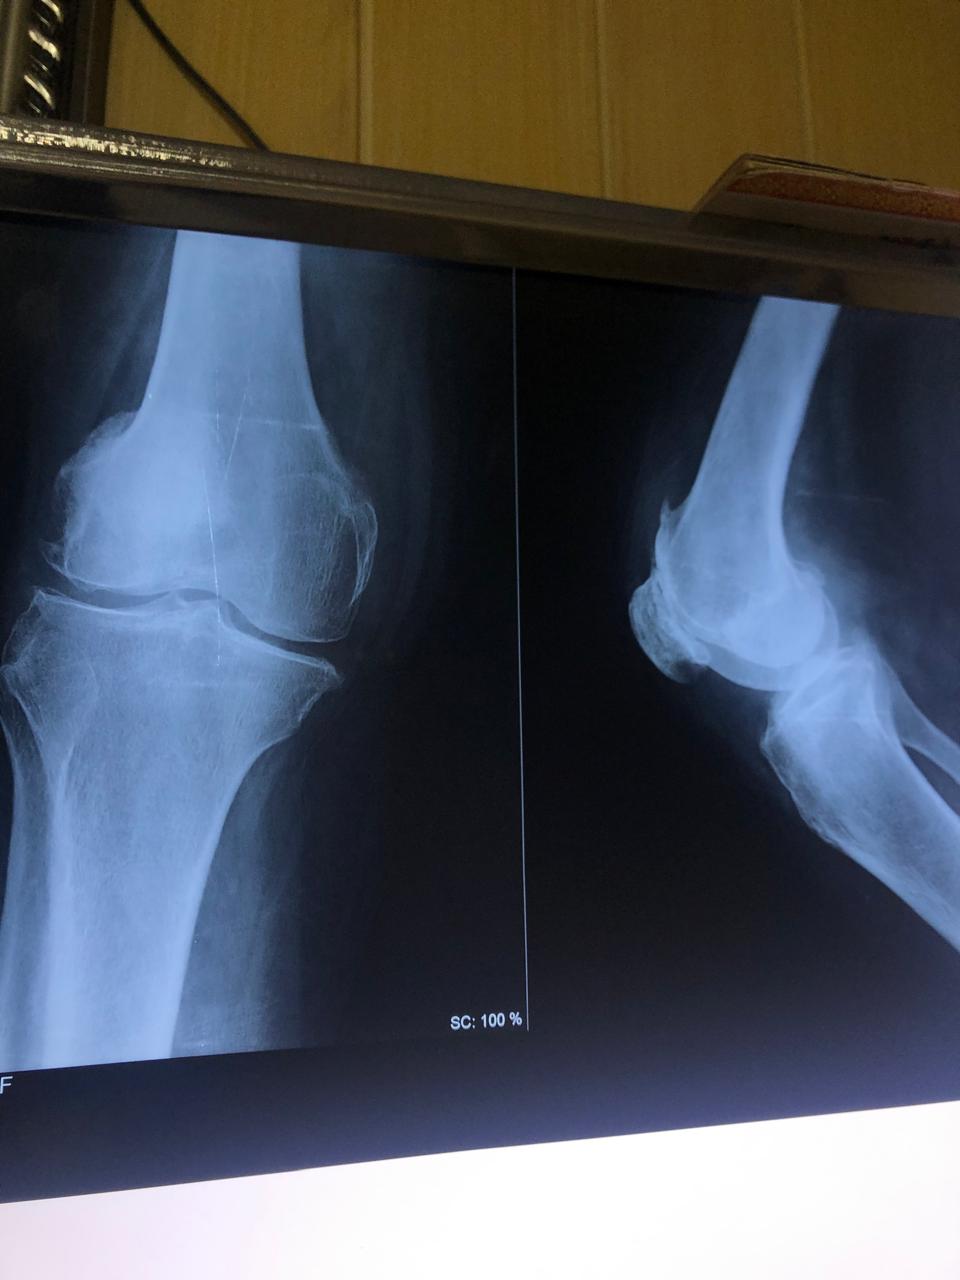

Joint replacement surgery is offered for patients suffering from severe joint pain, stiffness, and reduced mobility due to degenerative joint conditions. The goal of joint replacement is to relieve pain, restore movement, and improve overall quality of life through modern surgical techniques and structured post-operative care.

Total knee and total hip replacement surgeries are performed for advanced joint damage where conservative treatment is no longer effective. These procedures help restore joint function, reduce chronic pain, and allow patients to return to daily activities with improved mobility and comfort.